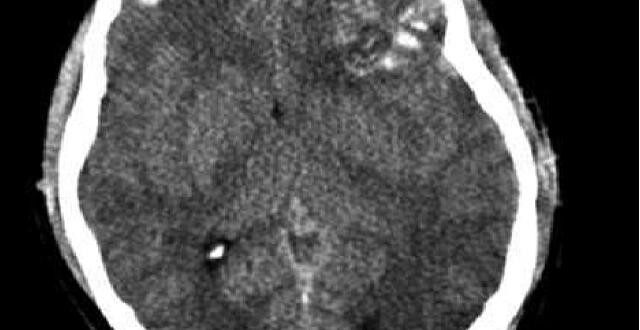

МКБ-10 Ушибленная рана головы по МКБ-10 относится к разделу S00-S09. А более конкретно к S06. S06.2 Диффузная травма головного мозга S06.3 Очаговая травма головного мозга Классификация По патофизиологии…

Симптомы Клиническая картина разделяется на 3 вида: общемозговой, подразумевает реакцию головного мозга на повреждение; локальный, зависит от области поражения, наибольшую опасность несут травмы, которые затрагивают продолговатый мозг; менингеальный,…